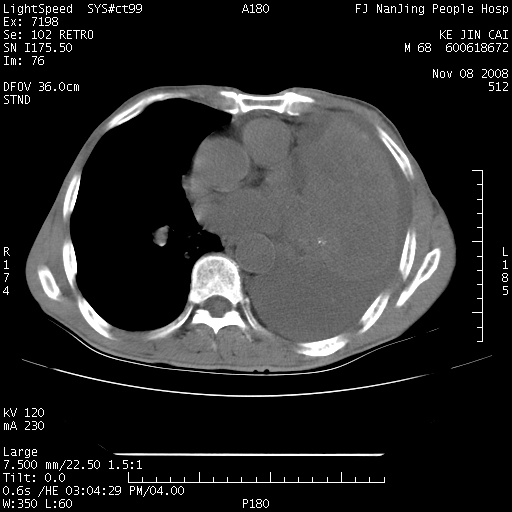

是个很有看头的病例,咋人气那么不旺?没多少人兴趣呢?这个病例几大怪:1   恶性肿瘤侵犯心肌左房怪,心肌一般不会被恶性肿瘤侵犯吧?2   左下肺均匀实变怪,内无含气,有别一般不张实变,含气肺泡完全为液体取代,而非一般不张实变的肺萎陷,冷不丁还以为是肿大的脾脏3   肿瘤本身怪,像tb肺不张4   这么有看头的病例没人气怪。呵呵。

左肺恶性肿瘤侵犯肺动脉,左心房内瘤栓,胸膜转移。

左肺恶性肿瘤侵犯肺动脉,左心房内瘤栓,胸膜转移,少见,学习了。